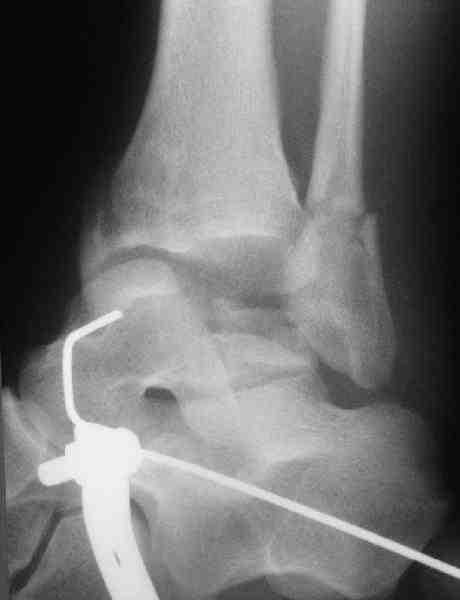

И второй случай из недавней ташкентской практики, (извините за качество ренгенограммы и только в одной проекции) случай падения с высоты (кстати моего друга - известного киноактера) - открытый

смещенный перелом тарана, с переломом переднего края дистального эпиметафиза большеберцовой кости.

При поступлении в приемной сделана первичная обработка с ушиванием открытой латеральной раны и вытяжением за пятку.

Из-за отсутствия времени пришлось оперировать на второе утро, из материала, что имеем на месте, фиксирован двумя шурупами, а третий-это контур сломанного жойстика в 4 мм. На дистальный медиальный конец тибиа antiglide 3.5 мм пластина. Через пару дней выписан и несмотря на предупреждение, самостоятельно начал нагрузку в 4 недели, время не ждет, снимается в боевике в Росийской Федерации.